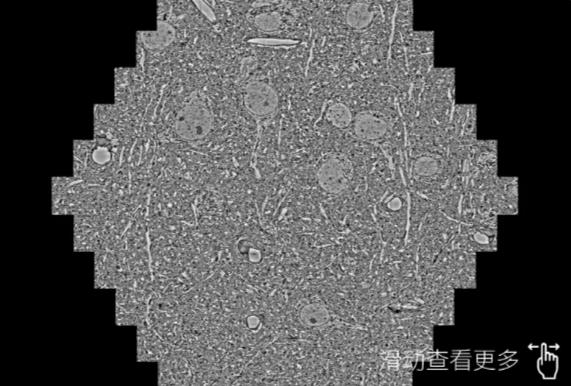

鼠脑切片。左图使用陵水蔡司陵水扫描电镜MultiSEM706对165μmx143pm面积区域成像,耗时仅需1.5秒。右图为鼠脑切片中30μm区域放大效果。样品由芝加哥大学B.Kasthuri提供。

使用蔡司高速陵水扫描电镜MultiSEM对1mm²人脑皮层组织进行高分辨成像,并对其中的各种细胞结构进行三维重构分析。左图展示了2x3mm²组织平面中锥体神经元的三维重构效果。右图显示了局部体积神经元三维重构。图像由哈佛大学chtman实验室提供,渲染图由D. Berger 制作。